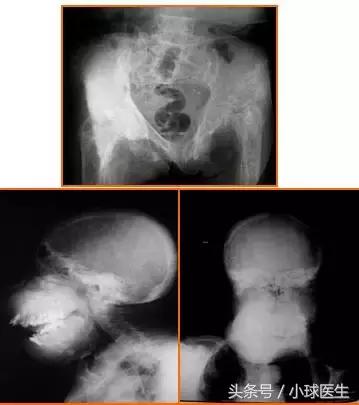

3、异常骨改变-骨骼畸形

4、异常骨改变-骨骼畸形

骨软化及继发性甲旁亢均可致骨骼畸形 。

骨盆口呈“心形”,四肢关节干骺端增宽、骨性关节面呈毛刷状改变,胸廓畸形呈鸡胸状 ,颌面骨呈“狮面”样改变 。